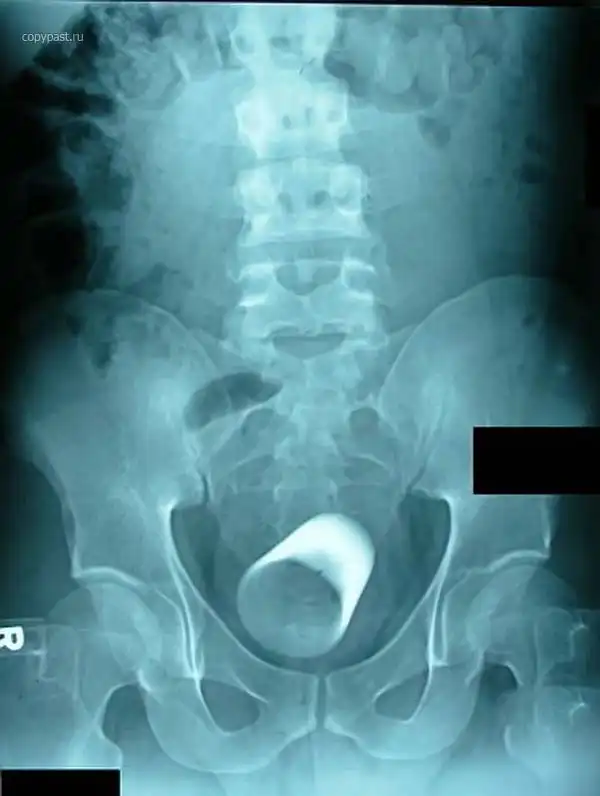

Пациент со стеклянной цилиндрической мензуркой в анусе. На уроках химии такого

не проходили

Огромный вибратор в заднице. Залез полностью. Без хирургического вмешательства

достать не смогли. Больные люди...